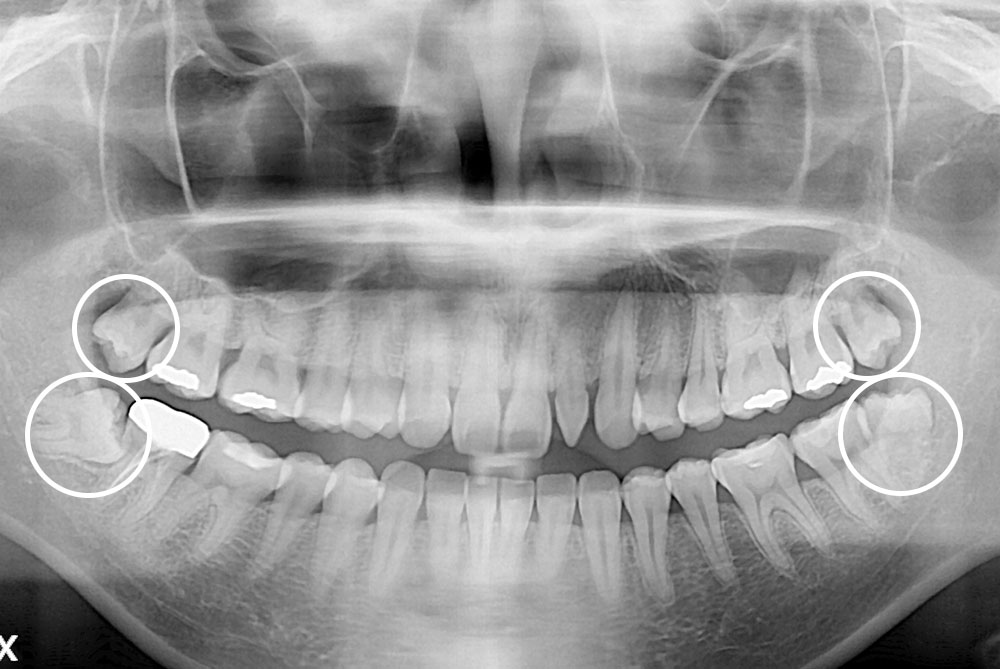

[사랑니] 매복 사랑니 발치

치료후 : 2024-01-17

세종치과는 구강악안면외과학 박사이신 원장님이 발치하는 치과입니다.